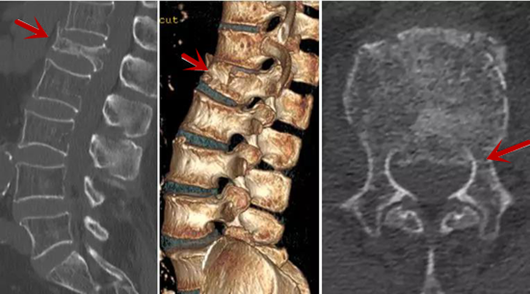

利器二:CT

CT利用X射線對(duì)人體檢查部位通過(guò)電腦切成若干層掃描,然后把每層的圖像都能顯示出來(lái)。CT相對(duì)于X光片具有更高的密度分辨力,可直接顯示X線片無(wú)法顯示的病變,觀察腰椎有無(wú)微小的骨折、骨質(zhì)有無(wú)破壞等骨質(zhì)情況、以及腰椎間盤突出、腰椎神經(jīng)根、椎管、椎間小關(guān)節(jié)的情況等。同時(shí)還可以通過(guò)后處理,重建腰椎矢狀位或冠狀位圖像,形成腰椎的3D圖像,更直觀地觀察病變部位,對(duì)腰椎手術(shù)風(fēng)險(xiǎn)具有提示作用,對(duì)手術(shù)方式的選擇具有指導(dǎo)意義,但是對(duì)神經(jīng)、脊髓損傷程度的顯示不如MRI,軟組織的分辨率仍有一定限制,對(duì)椎管內(nèi)病變顯示欠佳,且有一定的輻射。

從左向右依次為CT矢狀位重建圖像、三維重建圖像、軸位掃描圖像,箭頭提示腰1椎體爆裂性骨折